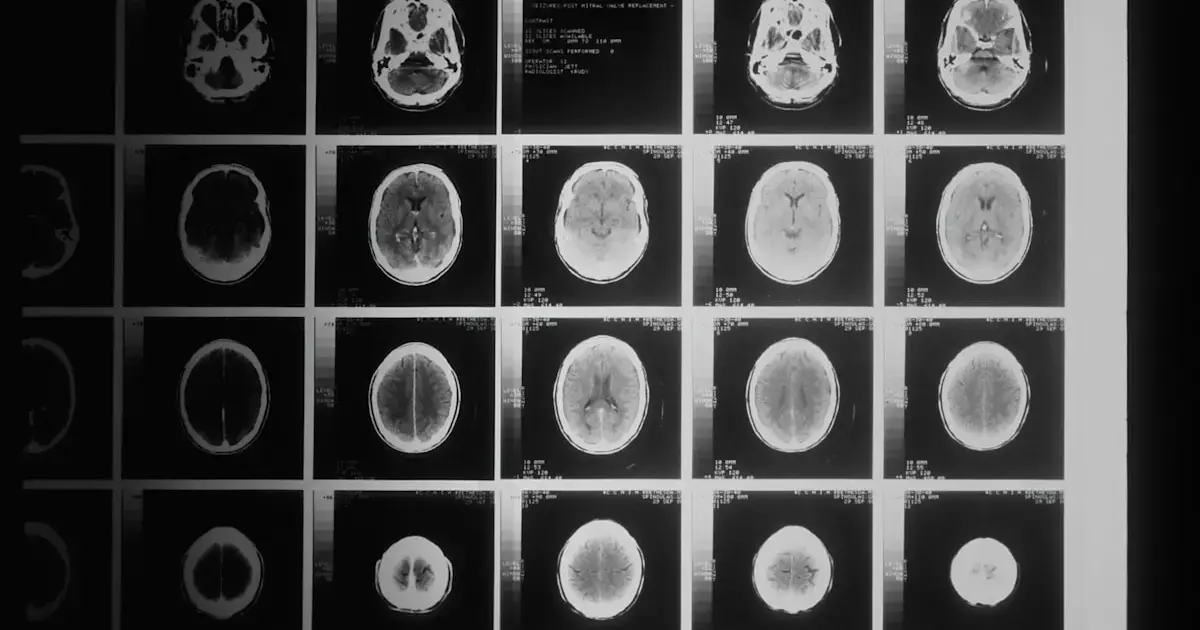

At the end of the experiment, brain scans showed that participants who adhered to the exercise regimen had brains that appeared, on average, 0.6 years younger than their chronological age. Meanwhile, those who did not exercise had brains that looked 0.35 years older, as reported by ScienceAlert.